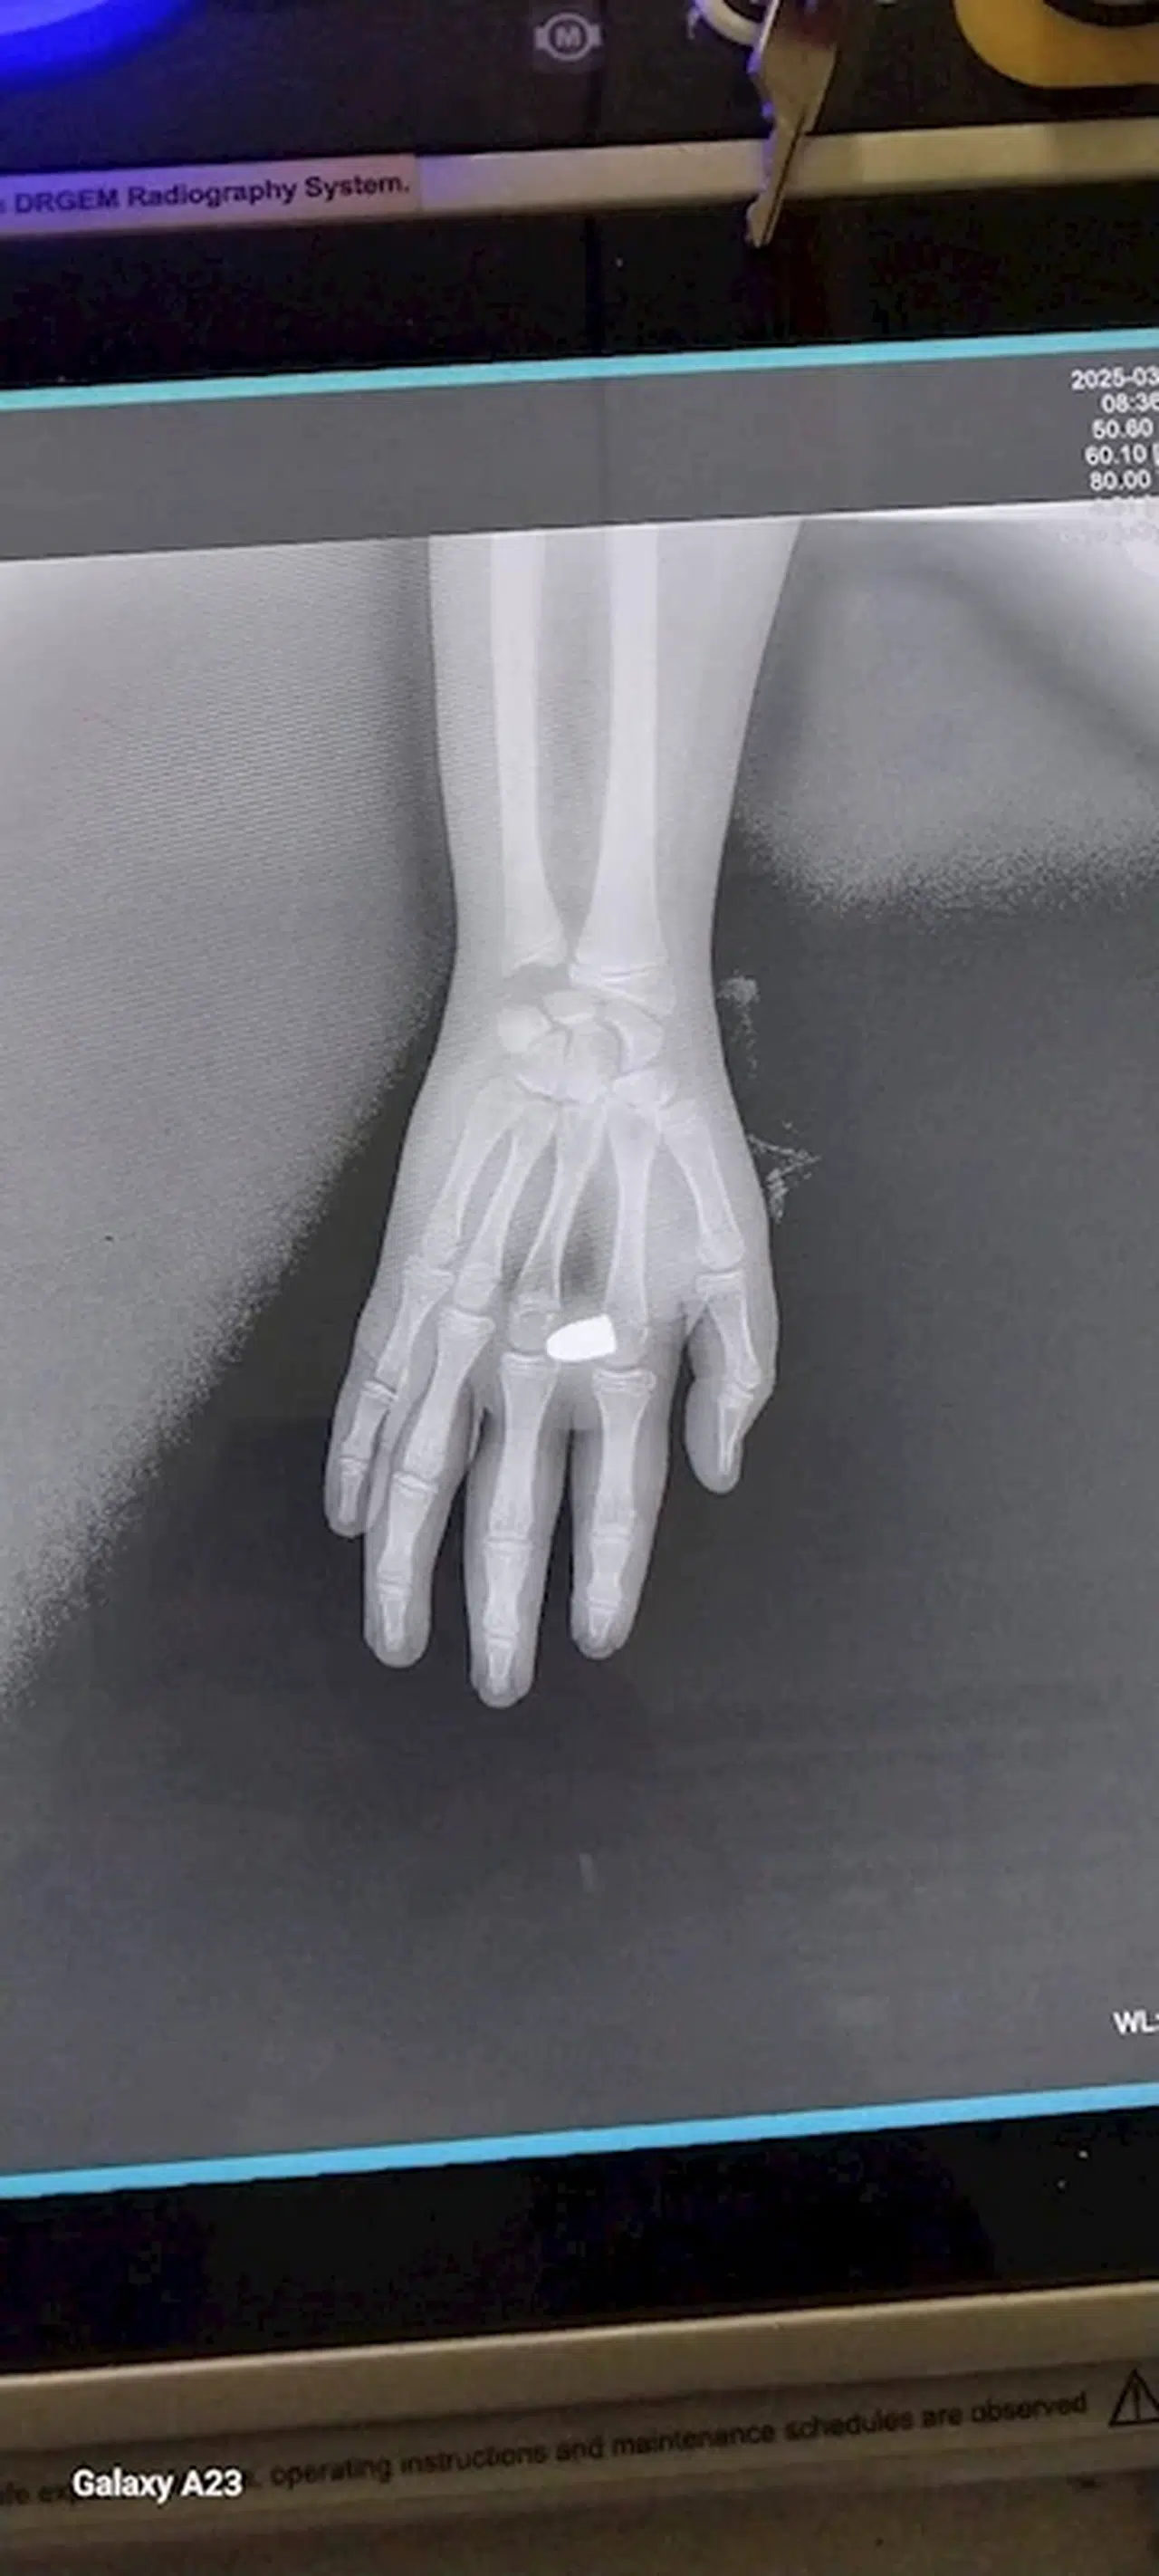

Tezcan SOLMAZ/KAYNAŞLI(Düzce),(DHA)-DÜZCE'nin Kaynaşlı ilçesinde eline yorgun mermi isabet eden Alperen K. (13) yaralandı.

Olay, dün sabah saatlerinde Kaynaşlı ilçesine bağlı Dipsizgöl köyünde meydana geldi. 'Bayram geleneği' adı altında bazı köy sakinleri, balkonlarından ve camlarından tabancalarla ateş açtı. Tabancaların birinden çıkan yorgun mermi, dışarıda olan Alperen K. isimli çocuğun sağ eline düştü. Alperen K., evine koşarak durumu ailesine haber verdi. Ailesi, kendi imkanlarıyla çocuğu Düzce Atatürk Devlet Hastanesi'ne götürdü. Burada, mermi çekirdeği doktorların operasyonuyla çıkarıldı. Olayla ilgili soruşturma başlatıldı. (DHA)

FOTOĞRAFLI